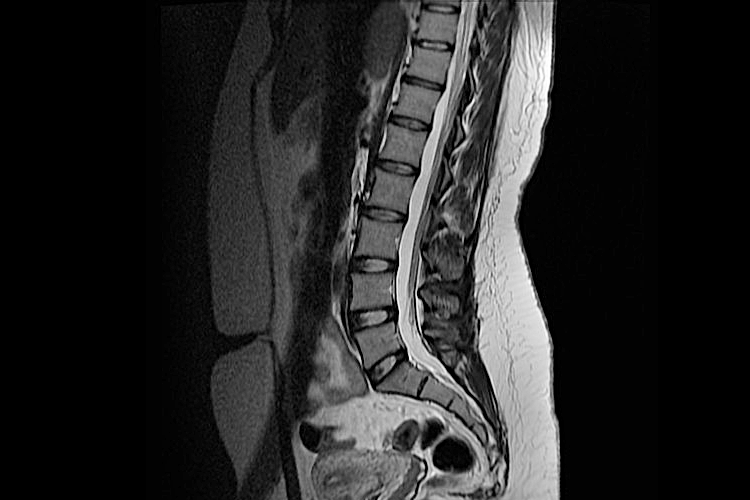

МРТ здорового поясничного отдела

На серии контрольных МР-томограмм, взвешенных по Т1 и Т2 в сагиттальной, корональной и аксиальной плоскостях физиологический лордоз выпрямлен на уровне Th12-L4, имеется С-образный изгиб вправо с ротацией тел позвонков. Отмечается смещение тела L2 кзади на 2 мм позвонка по отношению к нижележащему позвонку. Определяются дегенеративно-дистрофические изменения, характеризующиеся снижением высоты межпозвонковых дисков и интенсивности МР-сигнала от них на Т2 ВИ в разной степени выраженности. На фоне небольшого смещения тела L2 позвонка кзади имеется левосторонняя фораминальная протрузия L2-L3 межпозвонкового диска, размером до 4 мм, частично прикрытая краевыми костными разрастаниями, приводящая к умеренному сужению левого межпозвонкового отверстия. Отмечается небольшая до 2 мм левосторонняя дорзальная фораминальная протрузия L1-L2 диска, прикрытая краевыми костными разрастаниями с минимальным сужением левого межпозвонкового отверстия.

Визуализируются задние протрузии L3-L4, L4-L5, L5-S1 межпозвонковых дисков, частично прикрытые краевыми костными разрастаниями, до 3 мм, приводящие к деформации передней стенки дурального мешка, умеренному сужению межпозвонковых отверстий, на уровне L3-L4 больше справа. Отмечаются дегенеративные изменения дугоотросчатых суставов с субхондральным склерозом суставных поверхностей, небольшими краевыми костными разрастаниями по их контурам, сужением суставных щелей, выпотом в полость суставов, умеренной гипертрофии желтых связок, приводящие к минимальной деформации задней стенки дурального мешка и дополнительному сужению межпозвонковых отверстий. Данных за абсолютный стеноз позвоночного канала не получено.

Конус спинного мозга расположен обычно, МР-сигнал от него (по Т2 и Т1 ВИ) не изменен, нити конского хвоста имеют четкие контуры, МР-сигнал от них не изменен. Высота тел незначительно дегенеративно снижена, вдоль замыкающих поверхностей тел - краевые костные разрастания, передняя и задняя продольные связки уплотнены. Замыкательные пластинки тел позвонков имеют неровные контуры, «изъедены» с наличием хрящевых узлов Шморля. Отмечается трабекулярный отек костного мозга по типу асептического воспаления от смежных участков тел L1 и L2 позвонков в задних отделах. МР- сигнал от костного мозга остальных тел позвонков неравномерный за счет участков жировой дегенерации. Задняя группа мышц спины на уровне L3-S1 с признаками умеренно выраженной атрофии.

ЗАКЛЮЧЕНИЕ: МР-картина нарушения статики, ретроспондилолистеза тела L2 позвонка, дегенеративно-дистрофических изменений пояснично-крестцового отдела позвоночника в виде остеохондроза, деформирующего спондилеза, спондилоартроза, задний протрузий межпозвонковых дисков L1-S1. По сравнению с МР-данными от 2007 года динамика неоднозначная ранее выявленные грыжи дисков поясничного отдела не определяются, однако отмечается смещение тела L2 позвонка и появление зон отека костного мозга от смежных участков тел на уровне L1-L2.